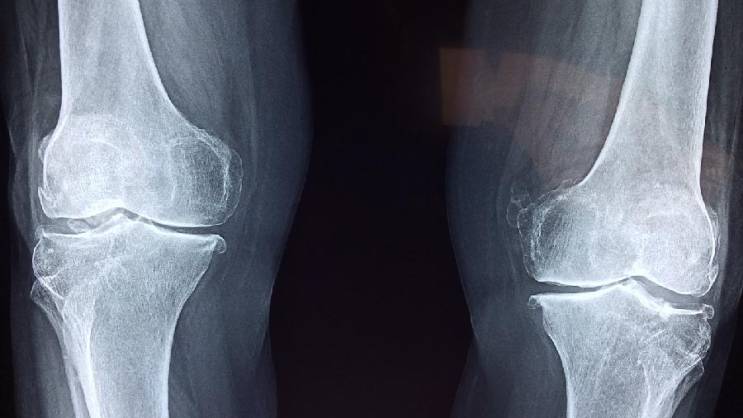

Foto: Ilustracija, Pixabay

Kosti često oslabe i postanu lomljive bez ikakvih simptoma, a toga postajemo svesni tek kada dođe do preloma.

„Pošto je slabljenje kostiju često neotkriveno, prvi način na koji ljudi mogu da saznaju koliko su im kosti zdrave je skeniranje gustine kostiju, ili DEKSA skeniranje, koje se preporučuje za svaku ženu stariju od 65 godina, mlađe žene u riziku od razvoja osteoporoze i muškarce starije od 70 godina“, rekao je za „The Parade“ dr Heter L. Hoflih.

„Nažalost, osteoporoza i osteopenija su često tiha stanja. Većina ljudi ne oseća ništa u svojim kostima dok ne dođe do preloma“, upozorila je ona.

Međutim, prema riječima dr Fišman, postoji rani znak da kosti slabe, a to je skupljanje.

„Dok neki ljudi vjeruju da je smanjenje obima zgloba znak slabljenja kostiju, to je zapravo manje tačan znak od gubitka visine“, primetila je ona.